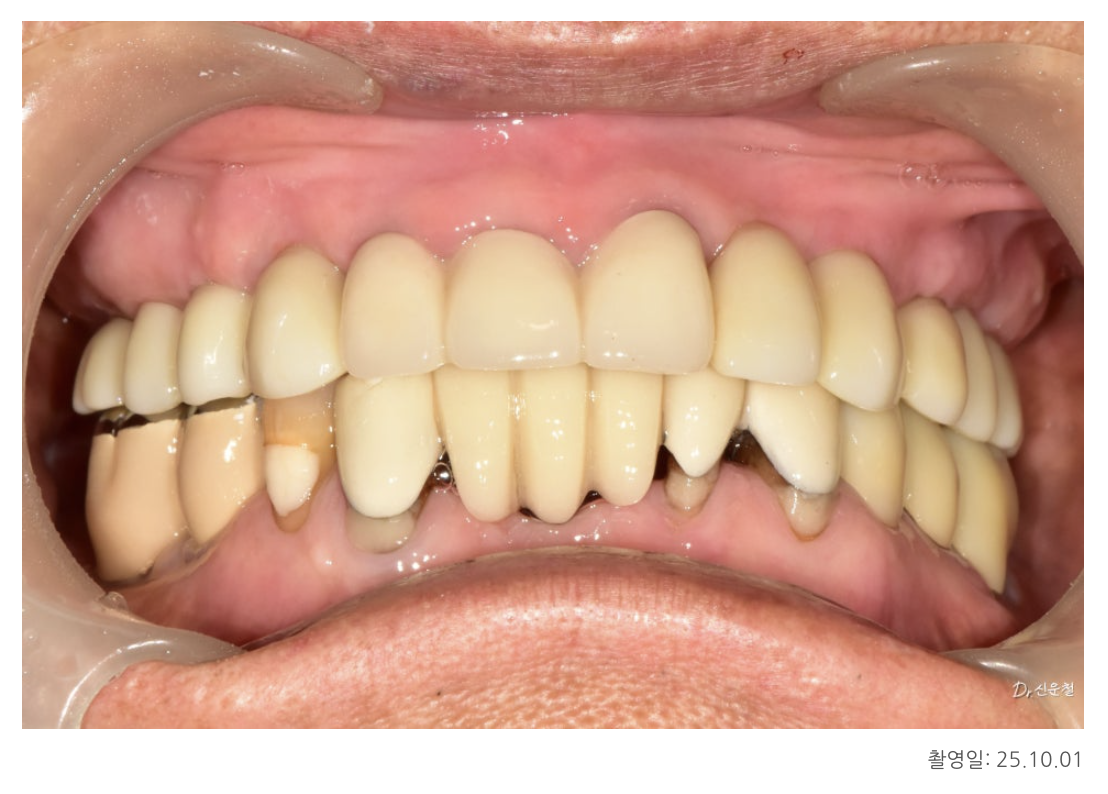

치료 결과

환자분은 치료 후

“이제 어느 쪽으로 씹어도 편하다” 고 가장 먼저 말씀하셨습니다.

전체적인 치아 복원에서 중요한 것은

치아를 얼마나 많이 만들었는가가 아니라,

“어디에 심어야 오래 버티는 구조가 되는가” 입니다.

이 원칙 덕분에

환자분은 이제 틀니 없이

편안한 식사가 가능한 상태가 되었습니다.